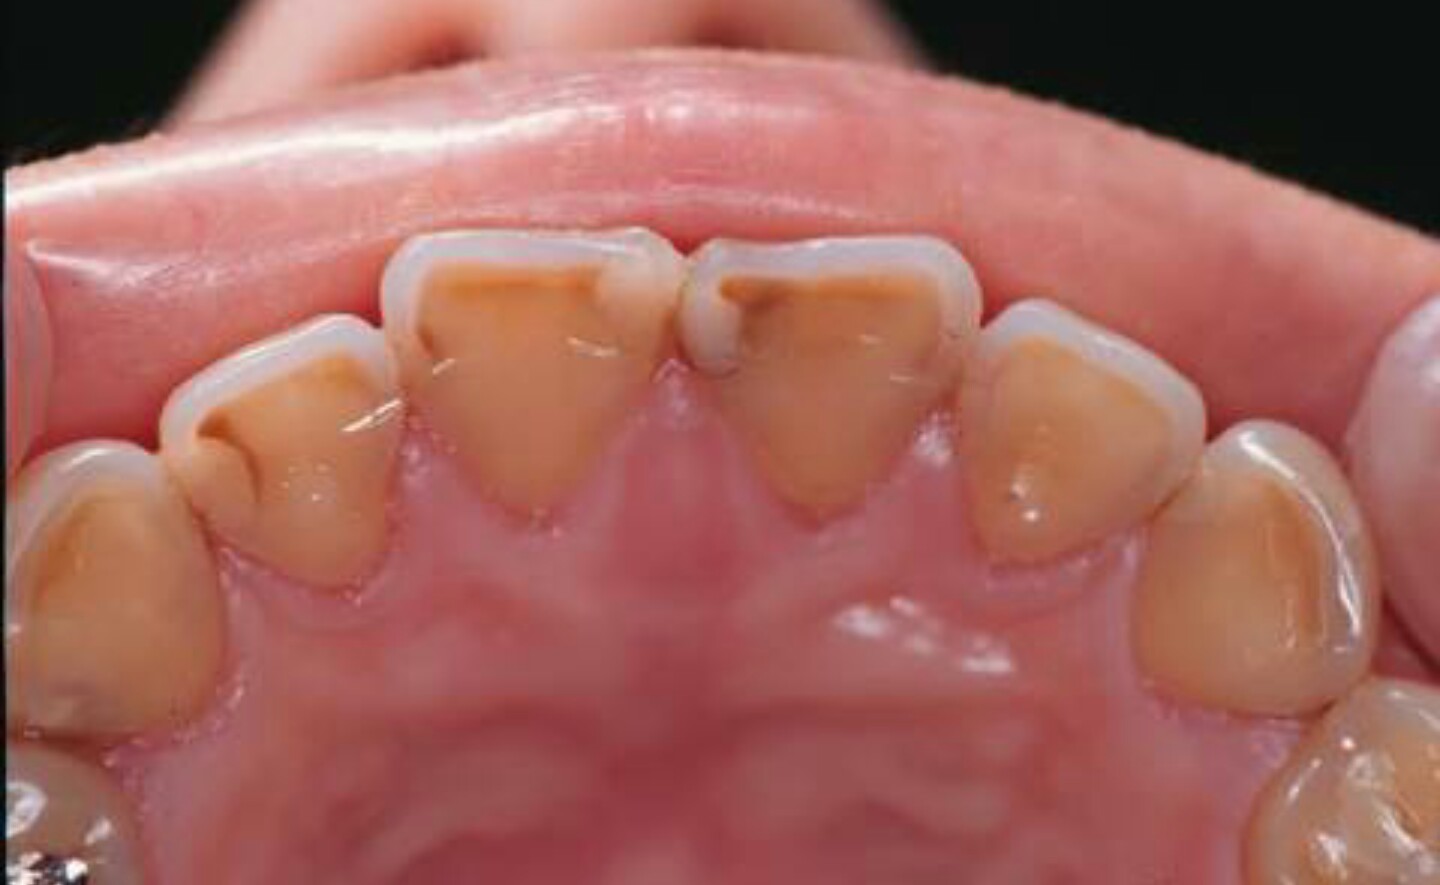

対合歯と接触する、歯の切縁並びに咬合面(対合歯と接触する部分)に欠損が発生する。軽度で咬耗がエナメル質に限局している場合は白色になる。象牙質まで達した場合、エナメル質と象牙質の硬度の差により、周囲のエナメル質の咬耗部と比較して象牙質の咬耗の度合いが強まる。咬耗は慢性的に少しずつ進むため、第二象牙質の形成により歯髄腔に達することは少ない。

対合歯との接触部に欠損がある場合、容易に咬耗症と診断できる。